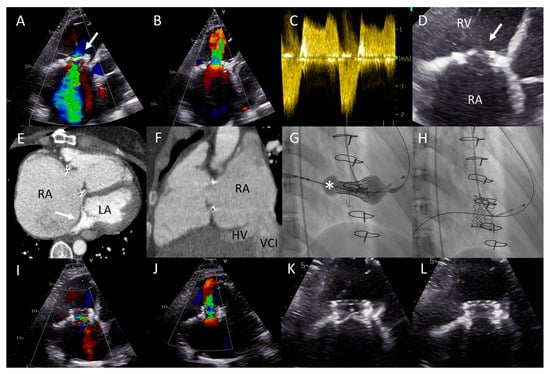

Figure 3.

(A) Color Doppler apical four-chamber view shows torrential tricuspid regurgitation (TR) with a wide vena contracta (arrow) and flow disturbance filling the enlarged right atrium. (B) Continuous wave doppler showing a dense TR signal with elevated right ventricular pressures. (C) Noncoaptation of the tricuspid valve (TV) leaflets (arrow) and annulus dilatation (dash line, 53 mm) is seen. (D) The hepatic vein Doppler demonstrates a pattern in atrial fibrillation with a prominent and late peaking systolic reversal (SR) wave. The only forward flow is evident in diastole (D-wave). (E) Two TR jets (a vena contracta of 4 and 7 mm, respectively, ERO of 90 mm2, regurgitant volume of 98 mL) are evident during transesophageal imaging. (F) Left anterior oblique and (G) right superior oblique fluoroscopic views showing patent right coronary artery (asterisk) and 18 anchors (arrows) between the two TV commissures allowing the Cardioband to significantly reduce the annulus dimensions. (H) Transesophageal echocardiography showing significant reduction in TR after the Cardioband annulus reduction procedure (appreciate the difference with panel (E), vena contracta of 3 and 5 mm, respectively, ERO 35 mm2, regurgitant volume of 41 mL).

The patient underwent a successful Cardioband annular reduction using right venous femoral access under general anesthesia with fluoroscopic (selective cannulation of the right coronary artery) and TEE guidance (Figure 3E–H). A total of 18 anchors were placed between the anteroseptal and posteroseptal commissure reducing the annulus dimensions to 45 × 36 mm. The torrential TR (two jets) was reduced to moderate TR (Figure 3E,H). At two years follow-up, the patient was in NYHA functional class I-II and no heart-failure-related admissions occurred. His NT-proBNP serum levels decreased to 2762 ng/L and at echocardiography he had a stable moderately reduced RV function and moderate TR.

Figure 4.

(A) Color Doppler apical four-chamber view shows severe tricuspid regurgitation (TR) with a wide vena contracta (arrow) and a systolic jet reaching the roof of the enlarged right atrium (RA). (B) Color Doppler showing turbulent inflow through the tricuspid valve (TV) bioprosthesis and aliasing, mean gradient was elevated at 4–5 mmHg. (C) Continuous wave Doppler showing a dense TR signal with low velocity. (D) Calcified and degenerated tricuspid bioprosthesis (arrow). (E) Axial slice through a computed tomography (CT) scan at the level of the right ventricle shows a giant RA and an intra-atrial septum deviation towards the left atrium (arrow), partially suppressing it. (F) Sagittal CT slice shows the inflow angle of the inferior vena cava-right RA and the RA-TV. Note the distended hepatic vein (HV). (G,H) Right anterior oblique fluoroscopy projections show the expansion of the Sapien 3 valve (asterisk) using the ring of the degenerated bioprosthesis as the reference and the final result, respectively. (I,J) Apical four-chamber color Doppler views showing normal function of the valve-in-valve bioprosthesis (appreciate the difference with (A,B), respectively). (K,L) View of the valve-in-valve bioprosthesis in systole (closed) and diastole (open), respectively.

This was successfully performed under local anesthesia, by means of right femoral access and fluoroscopy and TTE guidance. A temporary pacemaker wire was placed in the left ventricle and the AgilisTM steerable introducer (Abbott, IL, USA) was used to safely access the RA, given the relatively sharp angle between the vena cava-RA and the RA-RV axis (Figure 4F). The Edwards eSheath TM (Edwards Lifesciences, USA) was then used to implant a 29 mm Edwards SAPIEN 3 valve (Edwards Lifesciences) in the TVR bioprosthesis under rapid pacing (Figure 4G,H). Normal function of the new valve-in-valve bioprosthesis was confirmed by transthoracic echocardiography (Figure 4I–L). The periprocedural course was uneventful. At 22 months follow-up, the patient is in NYHA functional class I with moderately reduced (yet significantly improved) RV function and normal function of the bioprosthesis.

Figure 5.

(A) Distance between the right internal jugular vein and tricuspid valve (TV) measured on a computed tomography (CT) scan in a coronal plane (arrow). (B) Severely dilated mono-atrium (asterisk) on CT scan in a sagittal plane. (C) Implantation of the second XTW clip (note the first XTW clip already released) under transesophageal echocardiography (TEE) guidance. (D) Preprocedural TEE imaging of the torrential (IV+) TR. (E) Periprocedural TEE showing TR after placing the first XTW clip. (F) TEE showing the significant reduction in TR after placing the second XTW clip to grade I–II.

As a result of the severely dilated annulus and tethering, the coaptation gap was large, and simultaneous grasping of both leaflets was challenging. The TriClip system has the advanced option of independent leaflet grasping. First, the anterior leaflet (technically more challenging) was grasped and, subsequently, after minor device repositioning under TEE guidance, the septal leaflet was captured and the clip was released. The first clip was implanted near the commissure to narrow the coaptation gap so that the second clip could be implanted to treat the regurgitation (Figure 5C), which decreased to moderate (Figure 5E,F). Three weeks after the percutaneous procedure, at the outpatient clinic, the patient reported a decrease in orthopnea and exercise-induced dyspnea as the NYHA functional class was reduced from IV to III. At 17 months follow-up, the patient remained in NYHA functional class III. However, multiple heart-failure-related admissions occurred during follow-up (latest level of NT-proBNP was 8092 ng/L) and the patient developed atrial fibrillation (AF) which was treated with amiodarone.